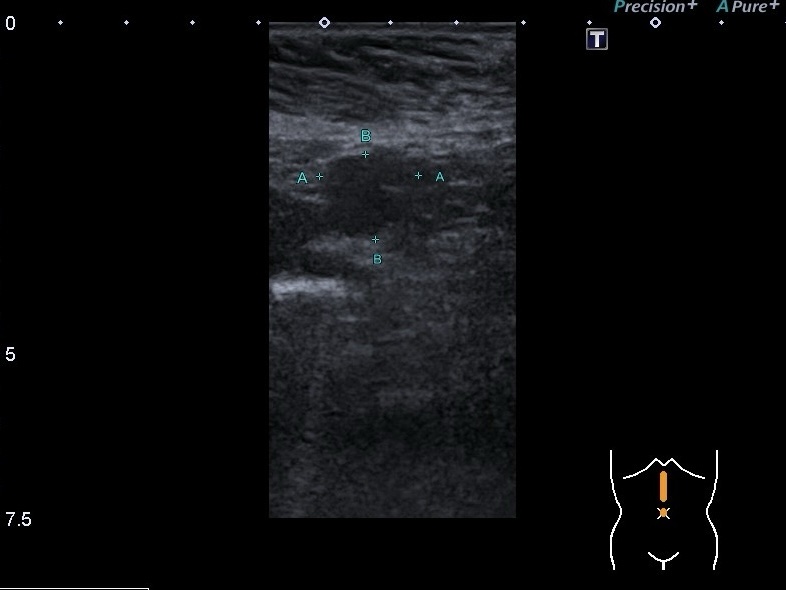

Ультразвуковая диагностика может обнаружить такие редкие патологии,как спленоз. Перед обследованием обязательно должен проводиться опрос жалоб и анамнеза жизни, заболевания. Это очень важный момент в диагностике. Например, недавно к нами обратилась пациентка с жалобами на боли при надавливании в области передней брюшной стенки. При распросе выяснилось, что в детстве пациентке удалили селезёнку вследствие её травмы. На УЗИ органов были выявлены множественные овальные солидные гипоэхогенные узлы в области брыжейки, сальника, между петлями кишки. Они были однородной структуры, чёткой овальной и округлой формы. Васкуляризация скудная. Один из узлов был над левою долей печени, достаточно поверхностно и при компрессии рукой или датчиком пациентка чувствовала боль.

Очень интересным был тот факт, что пациентка показала заключение компьютерной томографии, где стояло заключение карциноматоза брюшины. Но мы должны помнить,что при удалении селезёнки может возникнуть такое явление, как спленоз. Это состояние, при котором после травмы или удалении селезёнки её фрагменты приживляются в других местах брюшной полости и передней брюшной стенки. Даже известны случаи локализации в головному мозгу.

Спленоз у нашей пациентки был подтверждён с помощью биопсии.